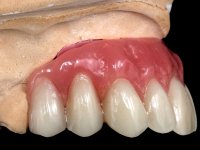

Após análise clínica e imagiológica foi proposto á paciente reabilitar o maxilar superior fazendo a colocação de 4 implantes e posteriormente ser reabilitada com uma Prótese Hibrida.Com a reabilitação proposta, também seria tentada a correção prostodontica da falta de apoio do lábio superior, desde que aprovada esteticamente pela paciente após um “Mock-up” prévio.

Inicialmente foram confecionadas duas novas próteses removíveis. O dente 1.3 foi extraído quando da colocação das próteses. Feito o estudo imagiológico necessário, foram colocados 4 implantes no maxilar superior. Após 3 meses de osteointegração foi feita a impressão para a confeção de ceras de articulação montadas em placa base aparafusadas aos implantes. Estas ceras foram utilizadas na recolha das relações inter-maxilares e na tentativa de proporcionar apoio ao lábio superior. Foi feita a prova de dentes com estes montados em placas base aparafusadas permitindo uma avaliação estética dinâmica muito interessante. Sendo validada esteticamente pela paciente, esta prova deu origem a uma muralha de silicone que orientou laboratorialmente a confeção da infraestrutura metálica. A infraestrutura metálica com os dentes montados em cera foi provada em boca, permitindo simultaneamente verificar a sua adaptação bem como a estética final. O trabalho final foi colocado em boca sendo acompanhado de instruções rigorosas de técnicas de higiene oral bem como da informação da necessidade de consultas de controlo periódicas.